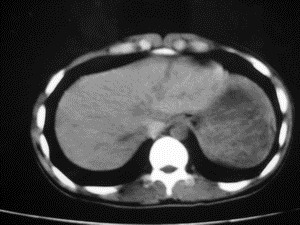

患者女,20岁,被车撞伤3小时,pe:全腹肌紧张,压痛反跳痛,以右上腹为著,肠鸣音减弱。有手术结果。![]() ![]() ![]() ![]() ![]() ![]() ![]() ![]() ![]() ![]() ![]() ![]() ![]() ![]() ![]() ![]() ![]() ![]() ![]() ![]() ![]() jiajie发言: ![]() 考虑空腔脏器穿孔。 dyqct发言:考虑:1、肝左叶外侧段断裂伤伴少量腹血。2、空腔脏器穿孔。 fangzheng发言:仅见腹腔内游离气体,提示空腔脏器穿孔。 guoke发言:胃内密度增高,肠腔内充满气体,考虑肠腔破裂出血 mmg94发言:胃后壁见一增厚软组织密度影,肝左叶前见游离气体影,左腹腔内局部肠管壁、系膜增厚。并见类圆形软组织。以上征象提示消化道管腔破裂,小肠、肠系膜挫裂伤,腹腔血肿形成。 拾荒者发言:肝实质密度不均匀,胃内见不均匀高密度影。考虑:肝挫裂伤,胃内应激性溃疡出血。 守望可可西里发言: 以下是引用jiajie在2006-6-20 15:49:00的发言:[br] [br][br]考虑空腔脏器穿孔。jiajie老师,我鼓起了很大的勇气才决定给您唱个反调儿,如果我错了,请您一定给我指出来,谢谢您了。我反复看了解剖图谱,觉得您所说的“考虑空腔脏器穿孔”上图所用箭头标明的不是游离气体。请您看以下几幅图片: ![]() ![]() ![]() ![]() ![]() ![]() ![]() ![]() 再请您看向医生老师发表的解剖图谱3幅 ![]() ![]() ![]() 这以下几幅图,我认为是肝包膜下积血。不过,说实在话,我没有发现有明显的肝挫裂伤。不对的地方请您一定指出来,再次感谢您了,jiajie 老师! ![]() ![]() ![]() ![]() 这下面几幅图片,我认为有明显的左中上腹部小肠损伤。 ![]() ![]() ![]() ![]() ![]() ![]() ![]() ![]() jiajie 老师,估计我说的是错误的,但我实在闹不明白,请您一定不要笑话我,并指出我的错误,以便于我减少工作中的失误。再次感谢您了,jiajie 老师! 至于胃内的不均匀高密度,我认为拾荒者战友说的有道理,胃内应激性溃疡出血和胃内容物混合所致。 手术结果:左肝叶(iv段)前缘长约8cm挫裂伤口,舌叶根部下< |